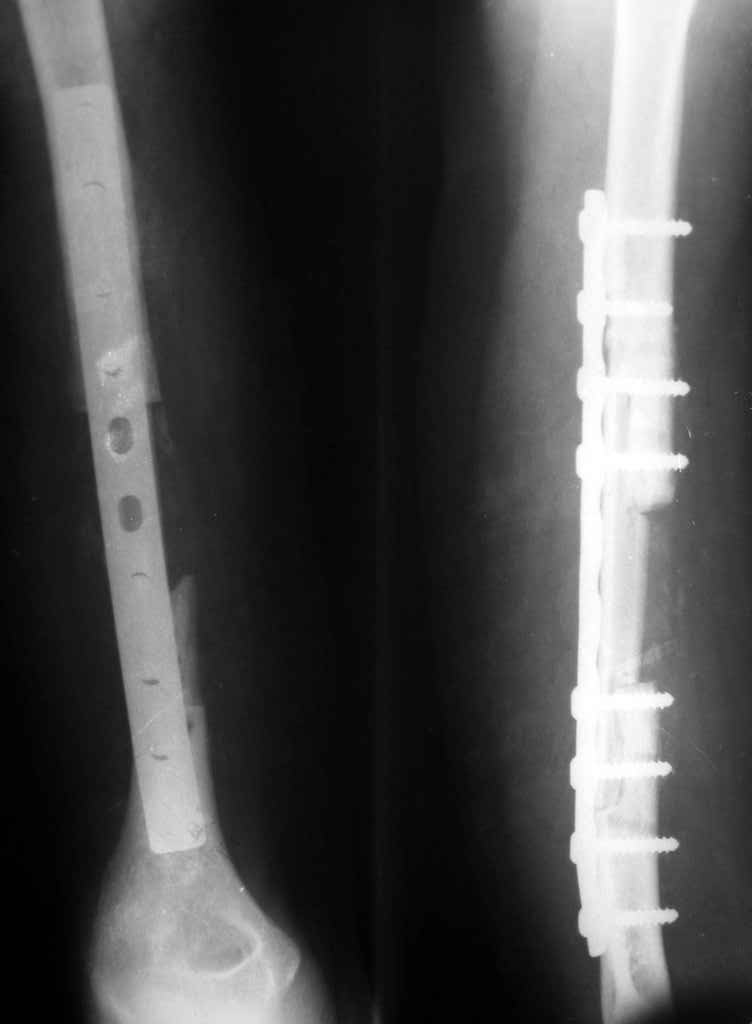

Владимир. Выделяем свои малоберцовую кость практически полность. Выпиливаем замок там и тут. Синтез. Нетипичный случай, но перестраивается хорошо даже диафиз. С уважением Дрягин